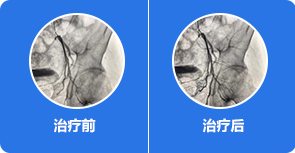

修复坏死骨质原因

清理、修复受损骨质,促进新骨再生

通过彻底清除关节腔内积液、炎症及游离物质,促进坏死骨质再生,改善跛行、受限症状,避免置换。

通过可视微创针镜,精准定位关节腔内炎症、积液及游离物质位置,有效清理,同时松解关节腔内粘连组织,为股骨头自我修复提供有利环境

治疗前:股骨头塌陷明显,骨质受损严重,关节间隙变窄

治疗中:股骨头受损骨质开始自我修复,关节间隙逐渐正常

治疗后:股骨头骨质修复完整,关节间隙正常